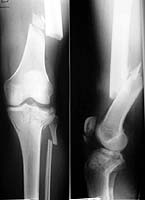

His general condition improved and he returned to the ward after 5 days at the intensive care unit. In the next 2 weeks all the fractures were subsequently treated by internal fixation.  In the left femur retrograde unreamed nailing was performed. Two screws were placed percutaneously in the patella. The tibial plateau fracture was treated by plate and screw osteosynthesis under fluoroscopic control.

Post-operatively, the knee was immediately put on a CPM machine. Despite our functional treatment 2 months after the accident his knee flexion is limited to 70 degrees; knee extension is normal. It is our impression that the flexion is limited by the (palpable) ossification around the femoral fracture. What are your suggestions about further treatment of this problem and how would you improve the knee function?